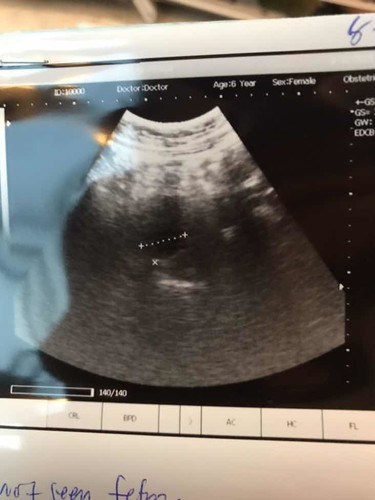

เจอแท้งคุกคามตอน 5 สัปดาห์ มีเลือดออก ประมาณ 1 วัน จนตอนนี้ 9 สัปดาห์ค่ะ ไปซาวน์มาวันนี้ ไม่เจอน้อง แต่ในใบซาวน์บอกได้ 8 สัปดาห์ หมอวินิจฉัยท้องลม แต่นัดซาวน์ใหม่อีก 1 อาทิตย์ เรายังหวังลึกๆในใจให้เจอน้อง ทั้งที่แทบจะไม่มีหวังเลย ใครเคยเจอเหตุการณ์แบบนี้บ้างค่ะ แล้วเจอน้องไหม ? เราว่าจะไปตรวจรพ. อีกที เพราะที่ไปซาวน์เป็นคลินิกค่ะ